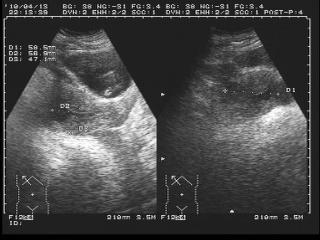

1、診斷方法:醫(yī)生會(huì)根據(jù)患者的病史、體征和輔助檢查來診斷宮外孕,常用的輔助檢查包括超聲檢查、血清人絨毛膜促性腺激素(hCG)測(cè)定等,醫(yī)生還會(huì)進(jìn)行詳細(xì)的婦科檢查以排除其他可能的疾病。